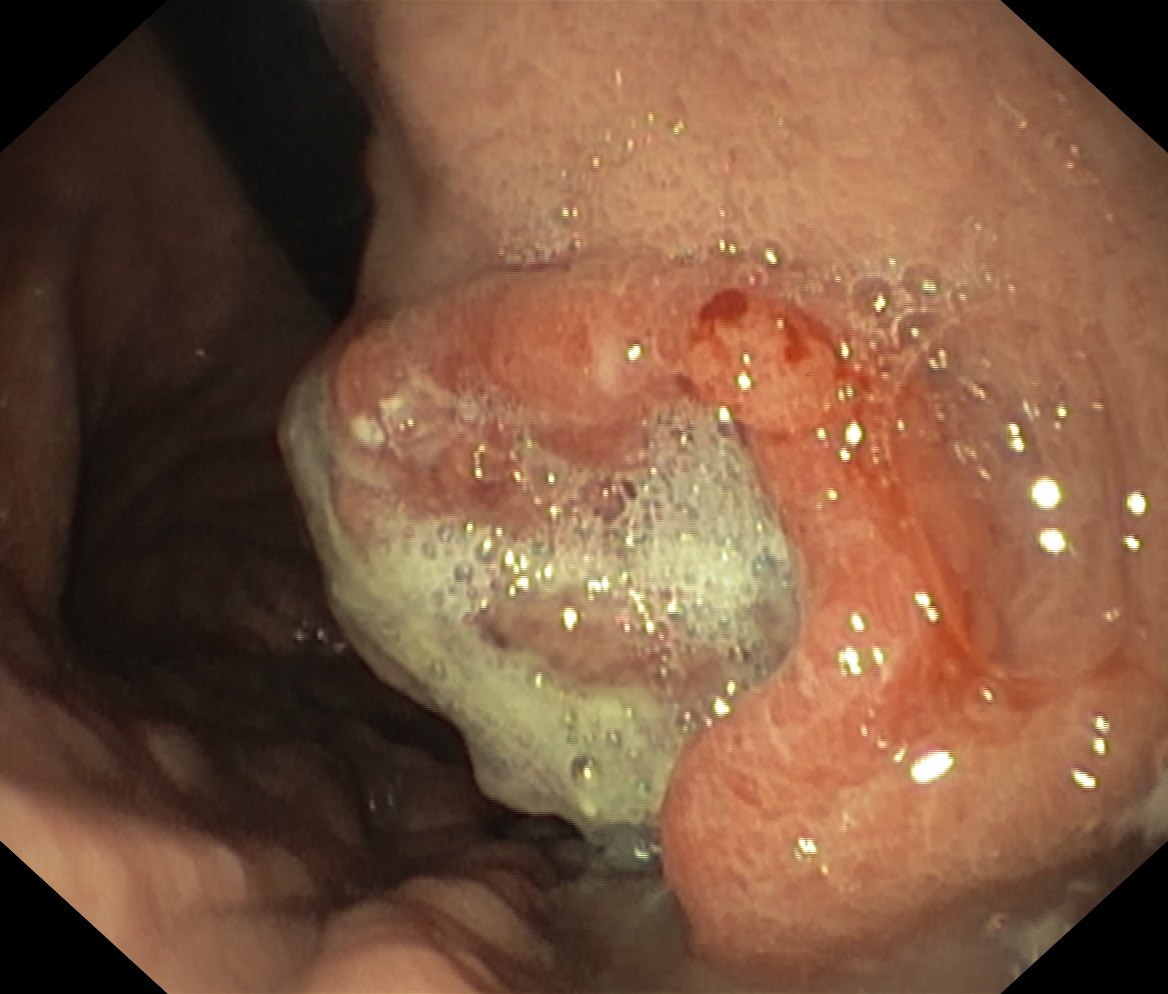

Nowotwory przewodu pokarmowego